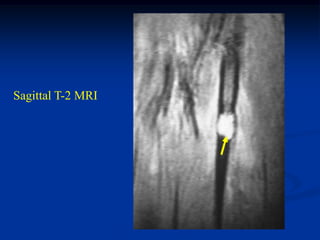

Sagittal T-2 MRI